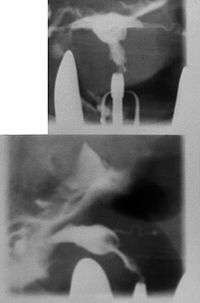

Women are often diagnosed with this condition after several failed pregnancies, proceeded by exploratory diagnostic procedures, such as magnetic resonance, sonography, and particularly hysterosalpingography.[6][7][8] In such studies, a widening of the interstitial and isthmus of uterine tube is observed, as well as constrictions or narrowing of the uterus as a whole, especially the lower and lateral portions, hence the "t" denomination. The uterus might be simultaneously reduced in volume, and other abnormalities might be concomitantly present.[9]